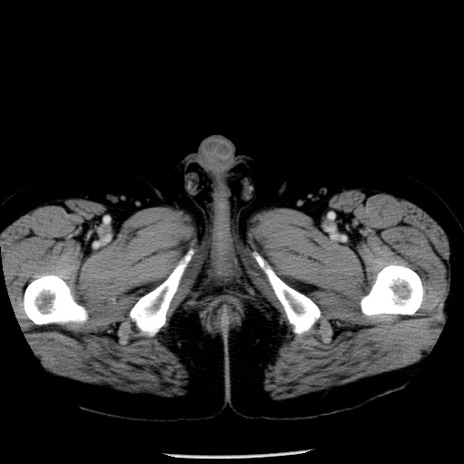

症例29(横断像)

【症例】40歳代男性

【現病歴】2日前から胃痛あり。徐々に周期的な激痛に変化した。本日になっても激痛があるため受診。

【身体所見】意識清明、BT 38-39℃台あり、腹部:膨満、やや硬、右下腹部に圧痛あり。

【データ】WBC 8500、CRP 23.26